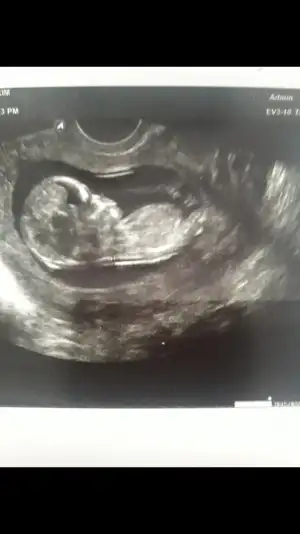

ben albüm yaptım, ilk benim gebeliğimden başlayan ultrason görüntüleri ile devam eden ve sonrasında yüzlerce fotosunun yer aldığı bir albüm.. yanlarına da notlar yazılan.. işte kilosu ne zaman yürüdü ne zaman anne dedi, büyüyünce onlar da soruyorlar cvp verebilirsin :))

Ultrason fotoğrafları kullandığım iğneler falan bende biriktiriyorum. Defter bende yapıcamda tekmelerini hissetmeye başlayınca yazıcam inşaallah. :)

erkek demişti demi dr. var mı 12. haftalarda fotosu nubdan da erkek mi :))

Erkek dedi. Alttan da karındanda bakmıştı o zaman hatta değişir mi dedim. Yok canım bak prda pipisi dedi de bizim heycandan gözümüz görmedi ki. Kontrole çok tedirgin gidiyprum ben sağlıklı dedikten sonra gerisini pek duymuyorum. Anlar mısın nubdan atayım

Screenshot_20181126-110108_Gallery.webp bu alttan görüntüsü. Ben nubdan anlamıyorum

ama bu alttan görüntü değil komple kafası gibi duruyor, o gördüğümüz nub kısmı ayaklara doğru gibi, o gördüğüm dik beyazlık o mu bende tereddüt ettim şimdi :KK48:

bende burda gördüğüm kadarıyla biliyorum canım :KK48: orda dik bir beyazlık var canım kızda o yatay oluyor.. muhtemelen erkek.. :KK200:

Sağlıklı olsun ilk çocuk farketmez zaten.doktor karından baktı ense kalınlığını ölçemiyorum dedi ben azıcık tombikimde. Alttan bakmak istedi bakın dedim bende. Her şeye baktıktan sonra dedi oğlunuz geliyor. Karından ilk bakıncada gördüm dedi. Özel doktor olunca cihazlar iyi diye düşünüyorm yanılmamıştır yani. :))

Alttan derken vajinal ultrason yoksa bacak arası görüntüsünü biliyorum canım. Mayıs annelerinde paylaşan vardı gördüm.